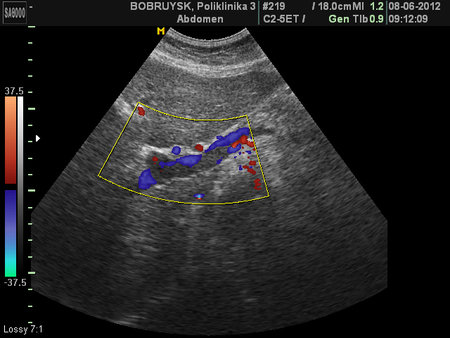

Неполный тромбоз воротной вены и ее ветвей

- Тромбоз правой и левой ветвей воротной вены

- ЦДК, промб в левой ветви ВВ.

- Порто-портальные коллатерали